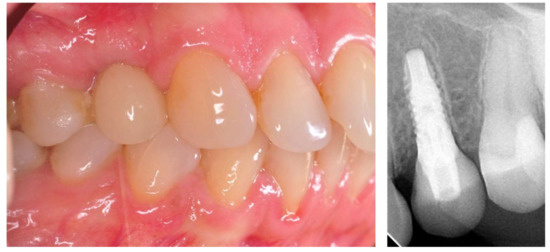

3.2. Results of Primary and Secondary Stability

The level of stability dropped within a period of four weeks of observation. The average primary stability (Ostell 0) achieved for a total of 40 implants was 71.59 ISQ (±4.04) and declined to 69.94 ISQ (±3.29) at the prosthetic phase (Ostell 1). The wider diameter of the implant provided a generally higher stability level, as the average results of the primary (72.30 ISQ (±4.56)) and secondary (70.39 ISQ (±3.29)) stability was higher for group two than for group one (70.84 ISQ (±3.39) and 69.50 ISQ (±3.31)), respectively (Table 1 and Figure 4).

3.3. Results of Marginal Bone Loss

The MBL in the 12-month follow-up period was higher in group one (0.26 mm (±0.31)) when compared to group two (0.14 mm (±0.24)) (Table 1 and Figure 5). The averaged MBL for all of the patients (groups one and two) was 0.2 mm (±0.88).

In our study, a decrease in the stability level in the four weeks following the implant insertion was observed (Figure 4). These results are in accordance with other studies and suggest the existence of bone resorption in direct contact with the implant surface. This behavior is attributed to the time dependency of bone remodeling observed at the initial stage. Therefore, the bone shape and remodeling toward the implant surfaces interfere with the bone-implant contact [18,19]. Carmo Filho, in the study on 4.0 and 4.1 mm diameter implants, reported the decline in implant stability at 21 days after surgery for the hydrophilic SLActive implants to 78.8 ± 2.6 ISQ, and to 78.4 ± 3.2 ISQ at 28 days for hydroxyapatite coated implants. However, hydroxyapatite coated implants regain the secondary stability much faster (42 days) when compared to SLActive implants (68 days) [19].

Aragoneses et al. included the implant diameter in the assessment of the levels of secondary stability. The ISQ value measured three months after the insertion of implants with a diameter of 3.7 mm was 69.62, while for implants with larger diameters (4.0 mm and 4.3 mm), that value was 72.02 and 69.67, respectively [27]. This finding is in agreement with the following study results (Figure 4 and Figure 5).

The lowest (0.22 ± 0.49 mm) MBL level of early loaded hydrophilic implants with the same, as presented in the following manuscript, observation period (12 months), to date, has been reported by Liaje et al. [30]. This finding of a low MBL was accompanied by high stability values at all time points (above 71 ISQ) and, similar to the presented study findings, (Figure 4) wide implants showed statistically higher stability values than narrow implants. On the contrary, much higher MBL levels than those found in our study for hydrophilic implants were reported by Ryu et al. (0.98 ± 0.61 mm) in 13 months of follow-up, and by Hinkle et al. (0.99 ± 0.29) in 12 months of follow-up [31,32].